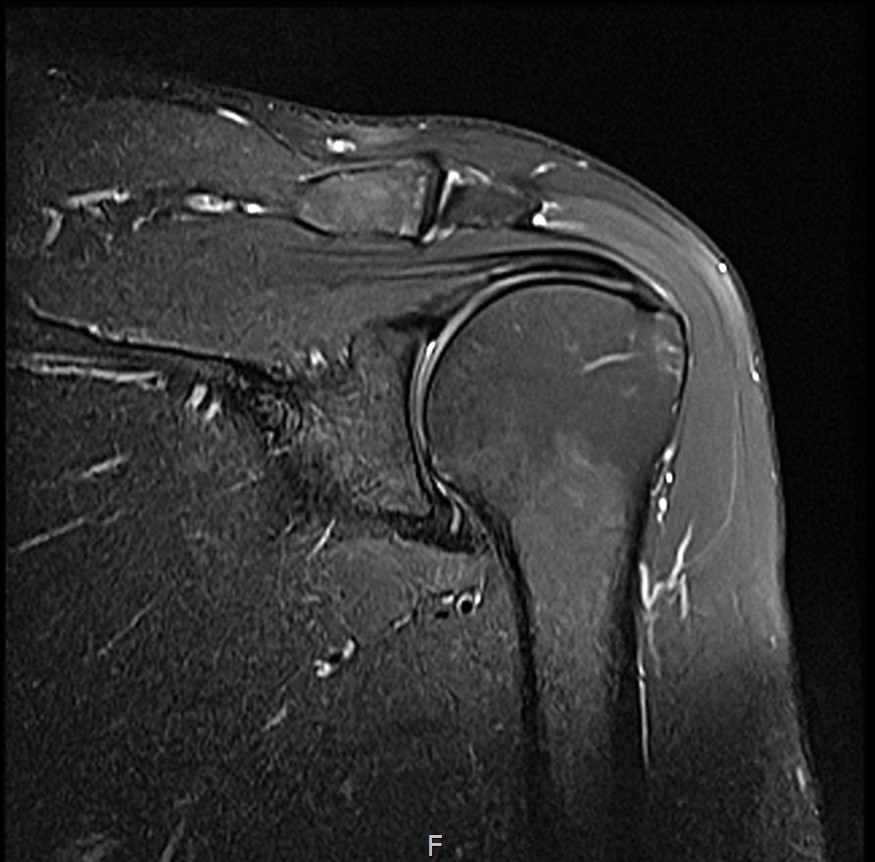

MRI: 극상건 점액낭면측 부분파열

인대 두께: 4.2mm (정상 5~6mm보다 얇음)

1년간 주사치료 3회, 반복 재발

6개월 후 MRI: 인대 두께 5.8mm (1.6mm 증가)

통증 소실

수영 복귀 (접영 제외, 자유형 위주)